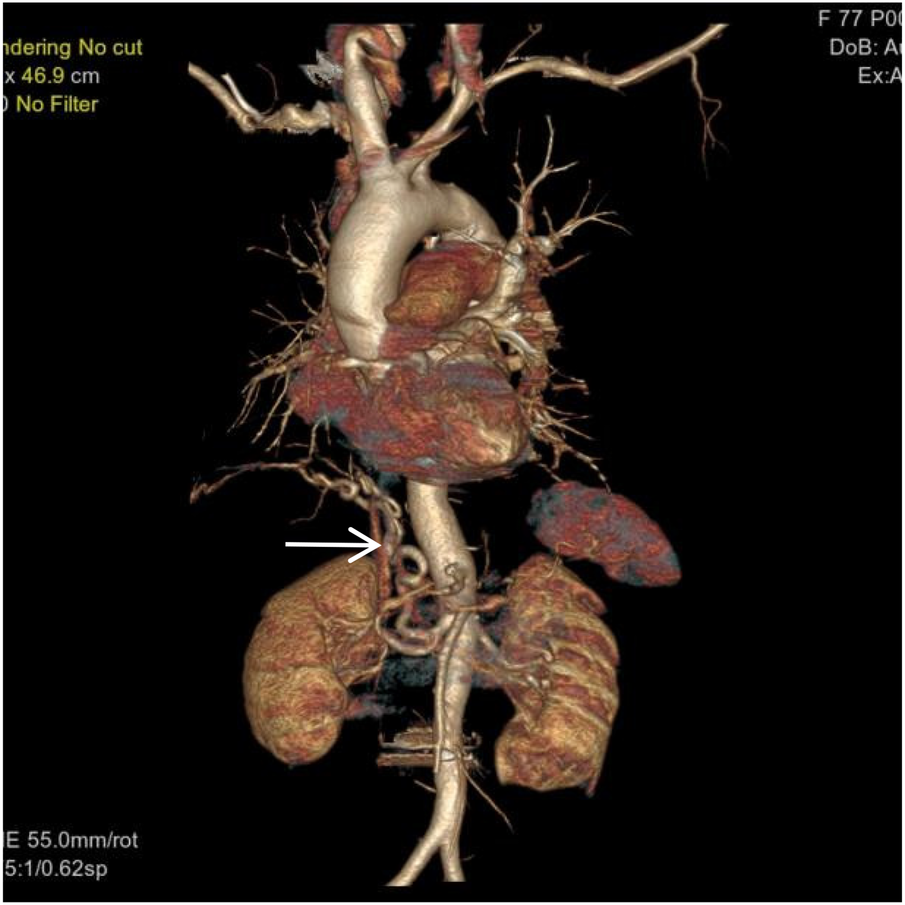

Figure 3

VR image shows a large, tortuous branch originating from the right renal artery entering the right lung (white arrow).

Figure 4

VR image shows a branch of the right subclavian artery entering the right lung (white arrow).

Thoracoabdominal aortic CTA and chest CT findings are illustrated in Figures 1–14. There was no evidence of aortic dissection. The right pulmonary artery was absent distal to approximately 3 cm from the bifurcation, with a smooth and rounded defect margin. The main pulmonary artery and its major branches showed no abnormal densities. No right pulmonary artery branches were observed in the right lung. Multiple tortuous arterial branches from the right subclavian artery, descending aorta, and right renal artery supplied the right lung. The right hemithorax was smaller, with localized pleural thickening and adhesions bilaterally. Multiple bronchiectasis with thickened walls and patchy, nodular, and linear opacities encircled the right lung. Increased translucency and several hyperlucent regions were visible in the left lung. CT imaging findings demonstrated: 1. Congenital absence of the right pulmonary artery (RPA), with the right lung supplied by collateral circulation originating from the right subclavian artery, right intercostal arteries, and the right renal artery. 2. Right pulmonary hypoplasia, bronchiectasis of the right lung, accompanied by infection and partial consolidation in the right upper lobe, compensatory hyperinflation of the left lung, and multiple bullae in the left lung. 3. Bilateral localized pleural thickening and adhesions. 4. Osteoporosis and mild flattening of the T6 vertebra and compression fractures of T11 and T12.